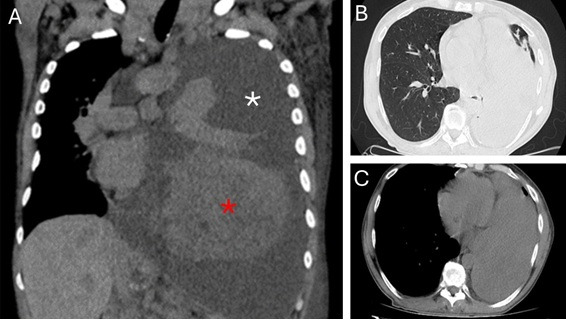

Clinical case: 63-year-old patient with a history of glomerulonephritis, hypothyroidism, arterial hypertension and a one-year diagnosis of solitary pleural fibrous tumor. Referred to endocrinology due to hypoglycemia for 6 months. Acromegaloid features were confirmed. Laboratory: Hct 36%, Hb 11.9 g/dl, GB 3570/mm3 (Eo 2%, Ba2%, Bac 4%, NS 36%, Li 30%, Mo 14% metamyelocytes 1%, myelocytes 11%), platelets 120,000 /mm3, ESR 10 mm, CRP 9 mg/L, TP 114%, TTPK 25 sec, blood glucose 57 mg/dL, renal function, hepatogram and lipid profile without particularities. IGF-1 84 ng/ml (VR 57 - 188), C-peptide 0.10 ng/ml (VR 1.10 - 4.40), somatotropin 0.98 ng/ml (VR up to 2.5) and basal insulin 0.4 uU/ml (VR 2.6 - 24) . IFG-2 measurement is not available in Argentina. A chest CT showed a pleural tumor measuring 13 cm. Without possibilities of surgical resection and without response to chemotherapy. Treatment was started with infusion of 25% dextrose, dexamethasone, pasireotide with good response. The patient died due to an infectious complication.